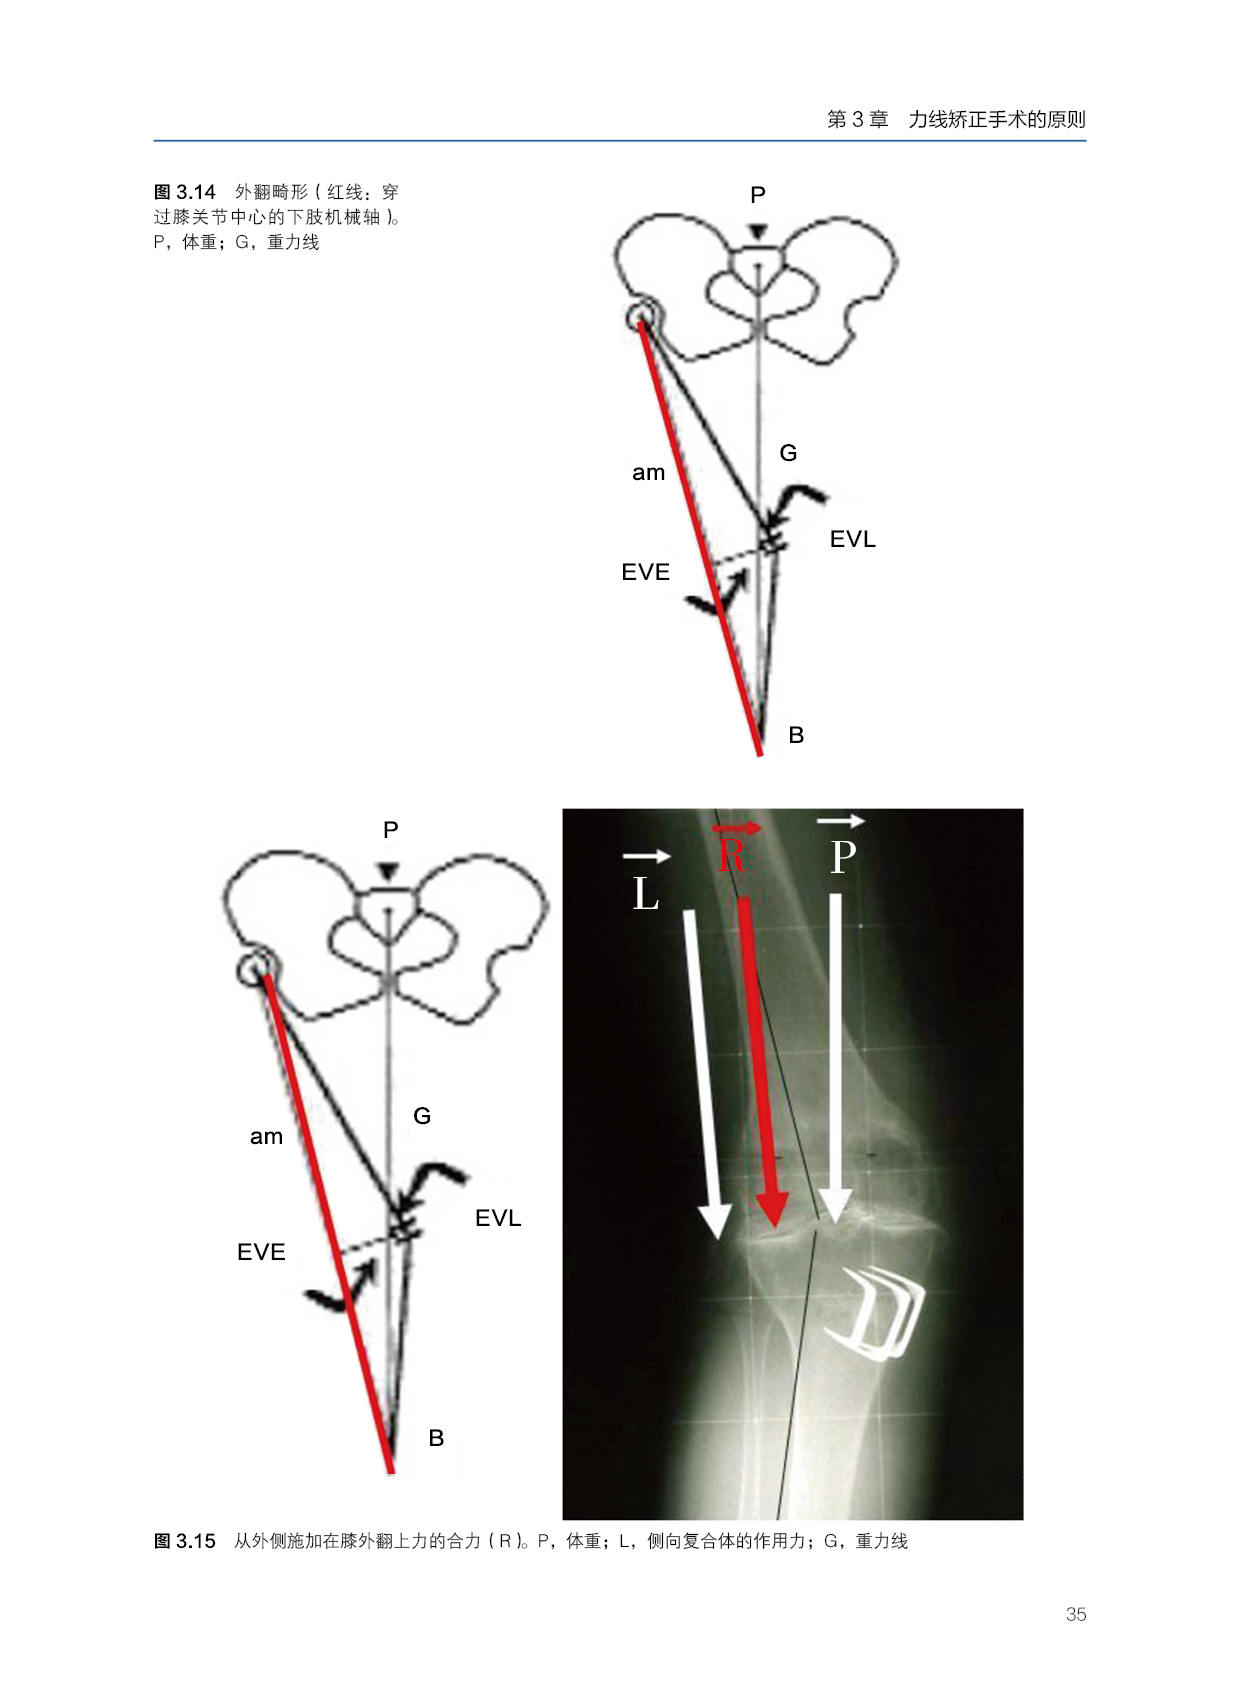

本书是进行保膝手术治疗退行性疾病和畸形相关膝关节不稳定的全面技术指南。根据他们在这些手术中的广泛经验,作者提供了有价值的见解,以确定哪些病人可能受益,以及计划和执行手术的高度精度,并解释可以实现的结果。本书重在介绍膝关节运动损伤的治疗理念。除了大量的真实病例,书中还分享了作者所在医院的整体管理和医生的治疗经验。